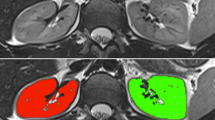

Segmentation of the entire kidneys and differentiation of their internal structures were performed in 12 healthy volunteers based on non-contrast-enhanced T1- and T2-weighted MR images. Two data sets (each acquired in one breath-hold) were co-registered using a rigid registration algorithm compensating for possible breathing-related displacements. An automatic algorithm based on thresholding and shape detection segmented the kidneys into their compartments and was compared to a manual labeling procedure.